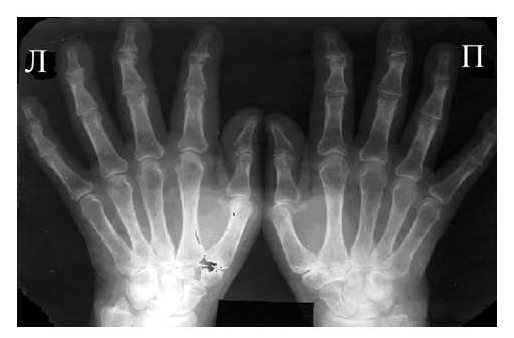

Рис. 3 Сочетание ревматоидного артрита и остеоартроза

Большинство ошибок встречаются при начальных стадиях, особенно при начале РА в пожилом возрасте и сочетании его с остеоартрозом (см. рис. 3). В этом случае для подтверждения диагноза РА и предупреждению случаев его гипердиагностики служит выявление симметричных эрозий в типичных для ревматоидного артрита суставах (запястья, плюснефаланговые, пястно-фаланговые).

Рис. 4. Изменения кистей при ревматоидном артрите (а остеопороз, бсужение суставных щелей, в кистовидные просветвления, г костные эрозии, д анкилозирование)

Необходимо также помнить, что, как правило, при РА эрозии не предшествуют околосуставному остеопорозу, кистам и сужению суставных щелей. Имеет место последовательность развития стадий РА (см. рис. 4), в отличие от эрозивных артритов другого генеза (псориатического, серонегативного)

Костные анкилозы выявляются только в суставах запястий и во 2-5-м запястно-пястном суставах, редко в лучезапястных и суставах предплюсны. Никогда анкилозы не формируются в межфаланговых суставах кистей и стоп, в первых запястно-пястных и плюснефаланговых суставах. Анализируя сроки появления основных рентгенологических проявлений наиболее типичным по нашим данным и по данным других авторов [LandeweR.] является появление первых симптомов РА (околосуставного остеопороза и кистовидных просветлений) через несколько месяцев (до года) от начала заболевания, эрозии выявляют на 2-3 год от начала заболевания.